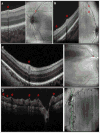

Methods: Bedside noncontact SD-OCT imaging was performed after obtaining parental consent on 97 consecutive infants between January 2009 and September 2012. Fifty-seven subjects (31-49 weeks' post-menstrual age) who had an SD-OCT scan in at least 1 eye showing the edge of the optic nerve and at least 1 major retinal vascular arcade were included. One eye per subject was randomly selected for analysis. Two masked graders evaluated scans for (1) retinal vessel elevation, (2) scalloped retinal layers, (3) hyporeflective vessels, and (4) retinal spaces. To coalesce the weight of these features, a Vascular Abnormality Score by OCT (VASO) was created. For quantitative assessment of vessel elevation, retinal surface maps were created.

Results: From among 67 SD-OCT characteristics that were recorded, the most common characteristics found were vessel elevation (44%), hyporeflective vessels (40%), scalloped layers (22%), and retinal spaces (11%). Features significantly associated with plus disease were vessel elevation (P = 0.01), hyporeflective vessels (P = 0.04), and scalloped retinal layers (P = 0.006). Intragrader agreement was between 74% and 90% for all features. The VASO was significantly higher in subjects with plus disease (P = 0.0013). On 3-dimensional SD-OCT volumes, eyes with plus disease had greater retinal surface elevation that more often matched en face retinal vascular patterns.

Conclusions: We present a novel 3-dimensional analysis of vascular and perivascular abnormalities identified in SD-OCT images of eyes with ROP. The SD-OCT characteristics that are more common in eyes with plus disease provide the first in vivo demonstration of the effects of vascular dilation and tortuosity on perivascular tissue. The VASO and surface maps also delineate the severity of vascular pathology in plus disease. Further studies evaluating these findings in eyes with pre-plus versus normal posterior pole vessels may determine the usefulness of SD-OCT in the early detection of vascular abnormalities in ROP.